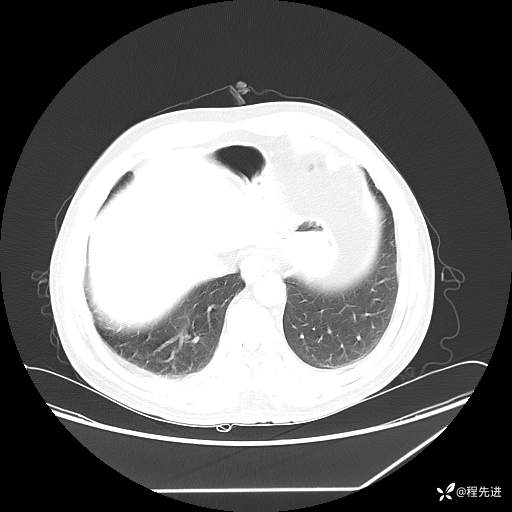

患者性别:男

患者年龄:57岁

简要病史:声嘶2月余

CT平扫+增强: